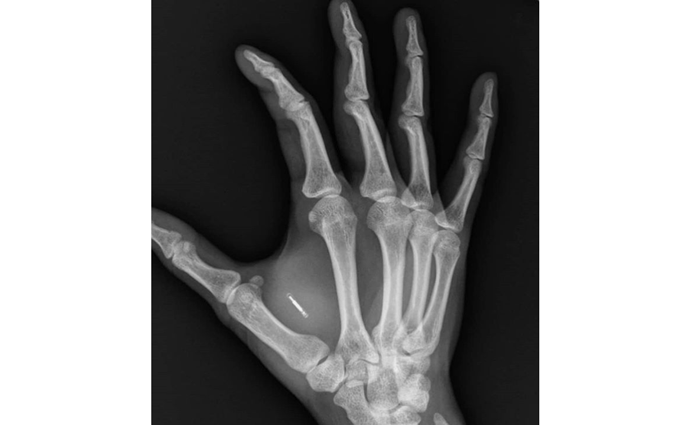

Već oko 4.000 ljudi u Švedskoj, nakon što je ta zemlja zakonom regulisala čipovanje, iskoristilo je mogućnost da između palca i kažiprsta jedne od šaka ugrade bio-čip.

Senzori veličine zrna pirinča, često i nevidljivi, po funkciji su pasivni, što znači da moraju da sadrže unaprijed zadate operacije ili ubačene podatke, koji kasnije mogu da se očitavaju sa njih iz neposredne blizine, koristeći se Near Field Communication (NFC) tehnologijom.